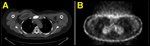

FIGURE 2

PET/CT Images Obtained at the Completion of AC Chemotherapy and 12 wk of Paclitaxel With Herceptin

After discussing the pros, cons, and unknown aspects of aggressive multi-modality therapy, the patient elected to pursue an aggressive approach. She has completed four cycles of doxorubicin/cyclophosphamide chemotherapy and 12 weeks of weekly paclitaxel with trastuzumab. She is on maintenance trastuzumab and has completed radiotherapy to her sternal metastasis. A repeat staging PET/CT scan after the chemotherapy but before radiation showed no new metastatic lesions and a dramatic decrease in the PET uptake in her sternal lesion (Figure 2). She has tolerated her treatment well thus far with no severe or unexpected toxicities.